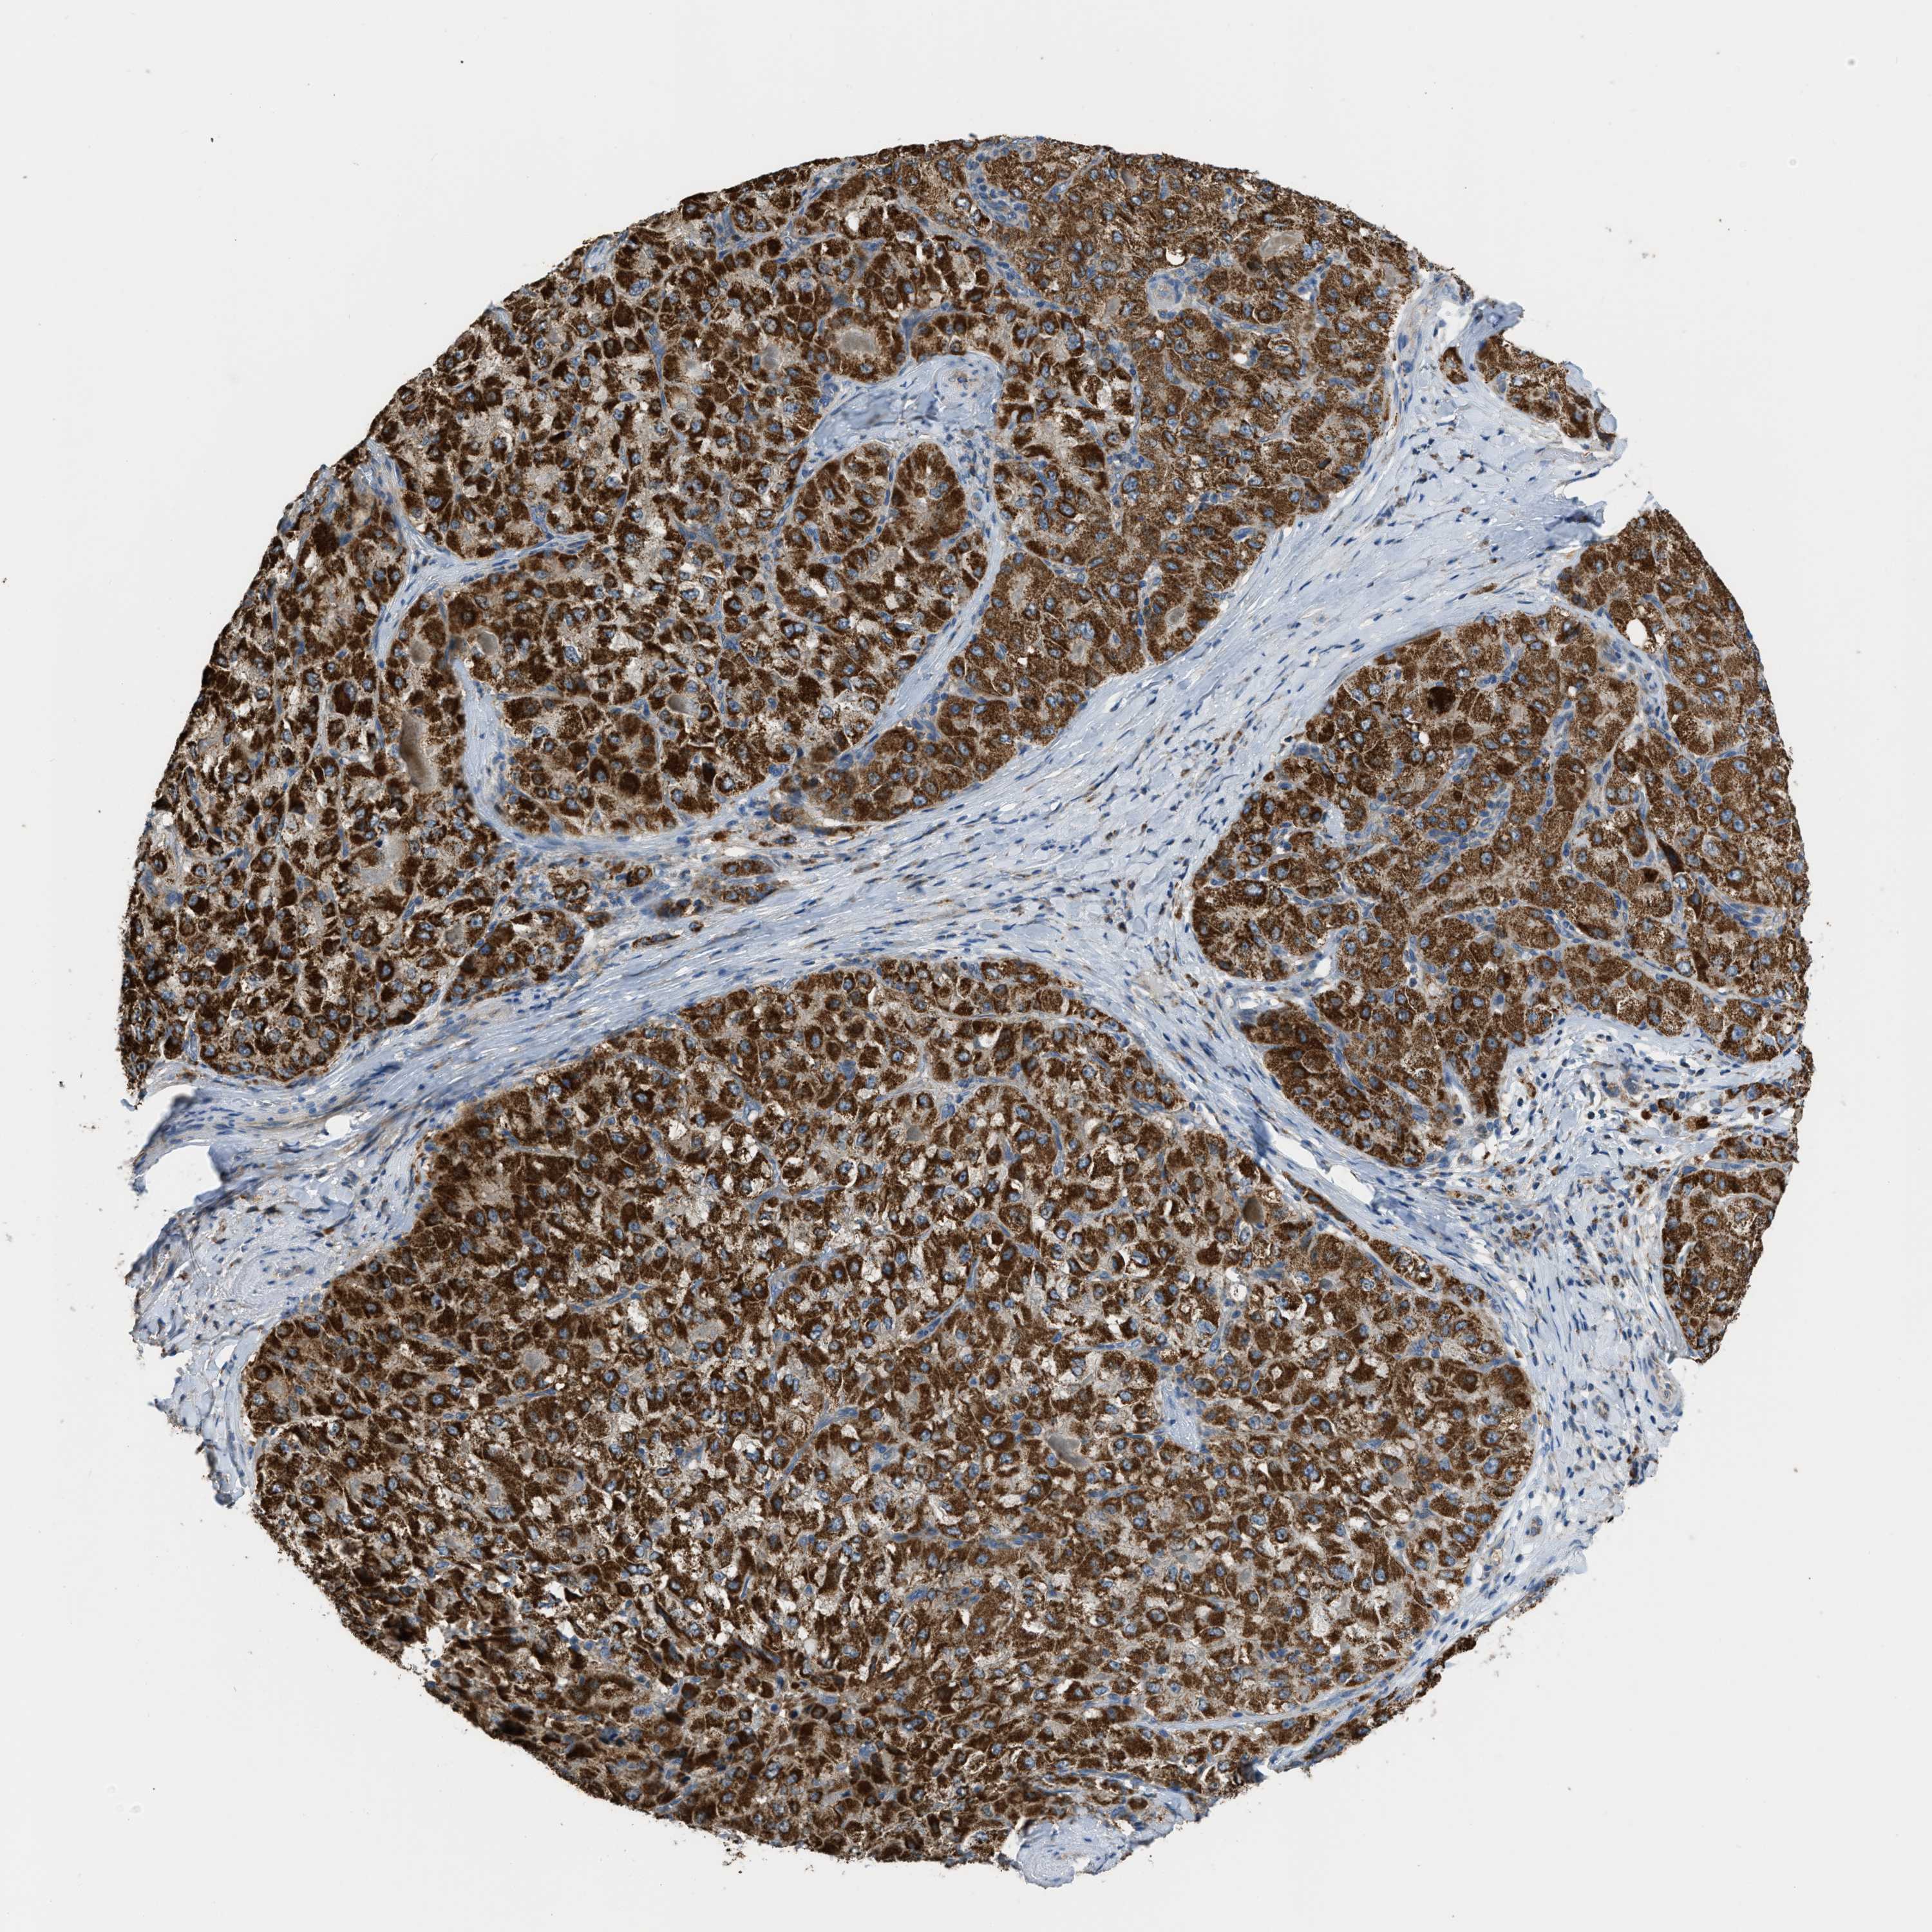

LIVER CANCER - Protein expressioni

A mouse-over function shows sample information and annotation data. Click on an image to view it in a full screen mode. Samples can be filtered based on level of antibody staining by selecting one or several of the following categories: high, medium, low and not detected. The assay and annotation is described here.

Note that samples used for immunohistochemistry by the Human Protein Atlas do not correspond to samples in the TCGA dataset.

Antibody stainingi

Antibody staining in the annotated cell types in the current human tissue is reported as not detected, low, medium, or high, based on conventional immunohistochemistry profiling in selected tissues. This score is based on the combination of the staining intensity and fraction of stained cells.

Each image is clickable and will lead to virtual microscopy that enables deeper exploration of all samples and also displays staining intensity scores, fraction scores and subcellular localization as well as patient and tissue information for each sample.

Antibody HPA018910

Antibody HPA018921

Antibody HPA018923

Staining

High

Medium

Low

Not detected

Intensity

Strong

Moderate

Weak

Negative

Quantity

>75%

75%-25%

<25%

None

Location

Nuclear

Cytoplasmic/membranous

Cytoplasmic/membranous,nuclear

Cholangiocarcinoma

Carcinoma, Hepatocellular, NOS